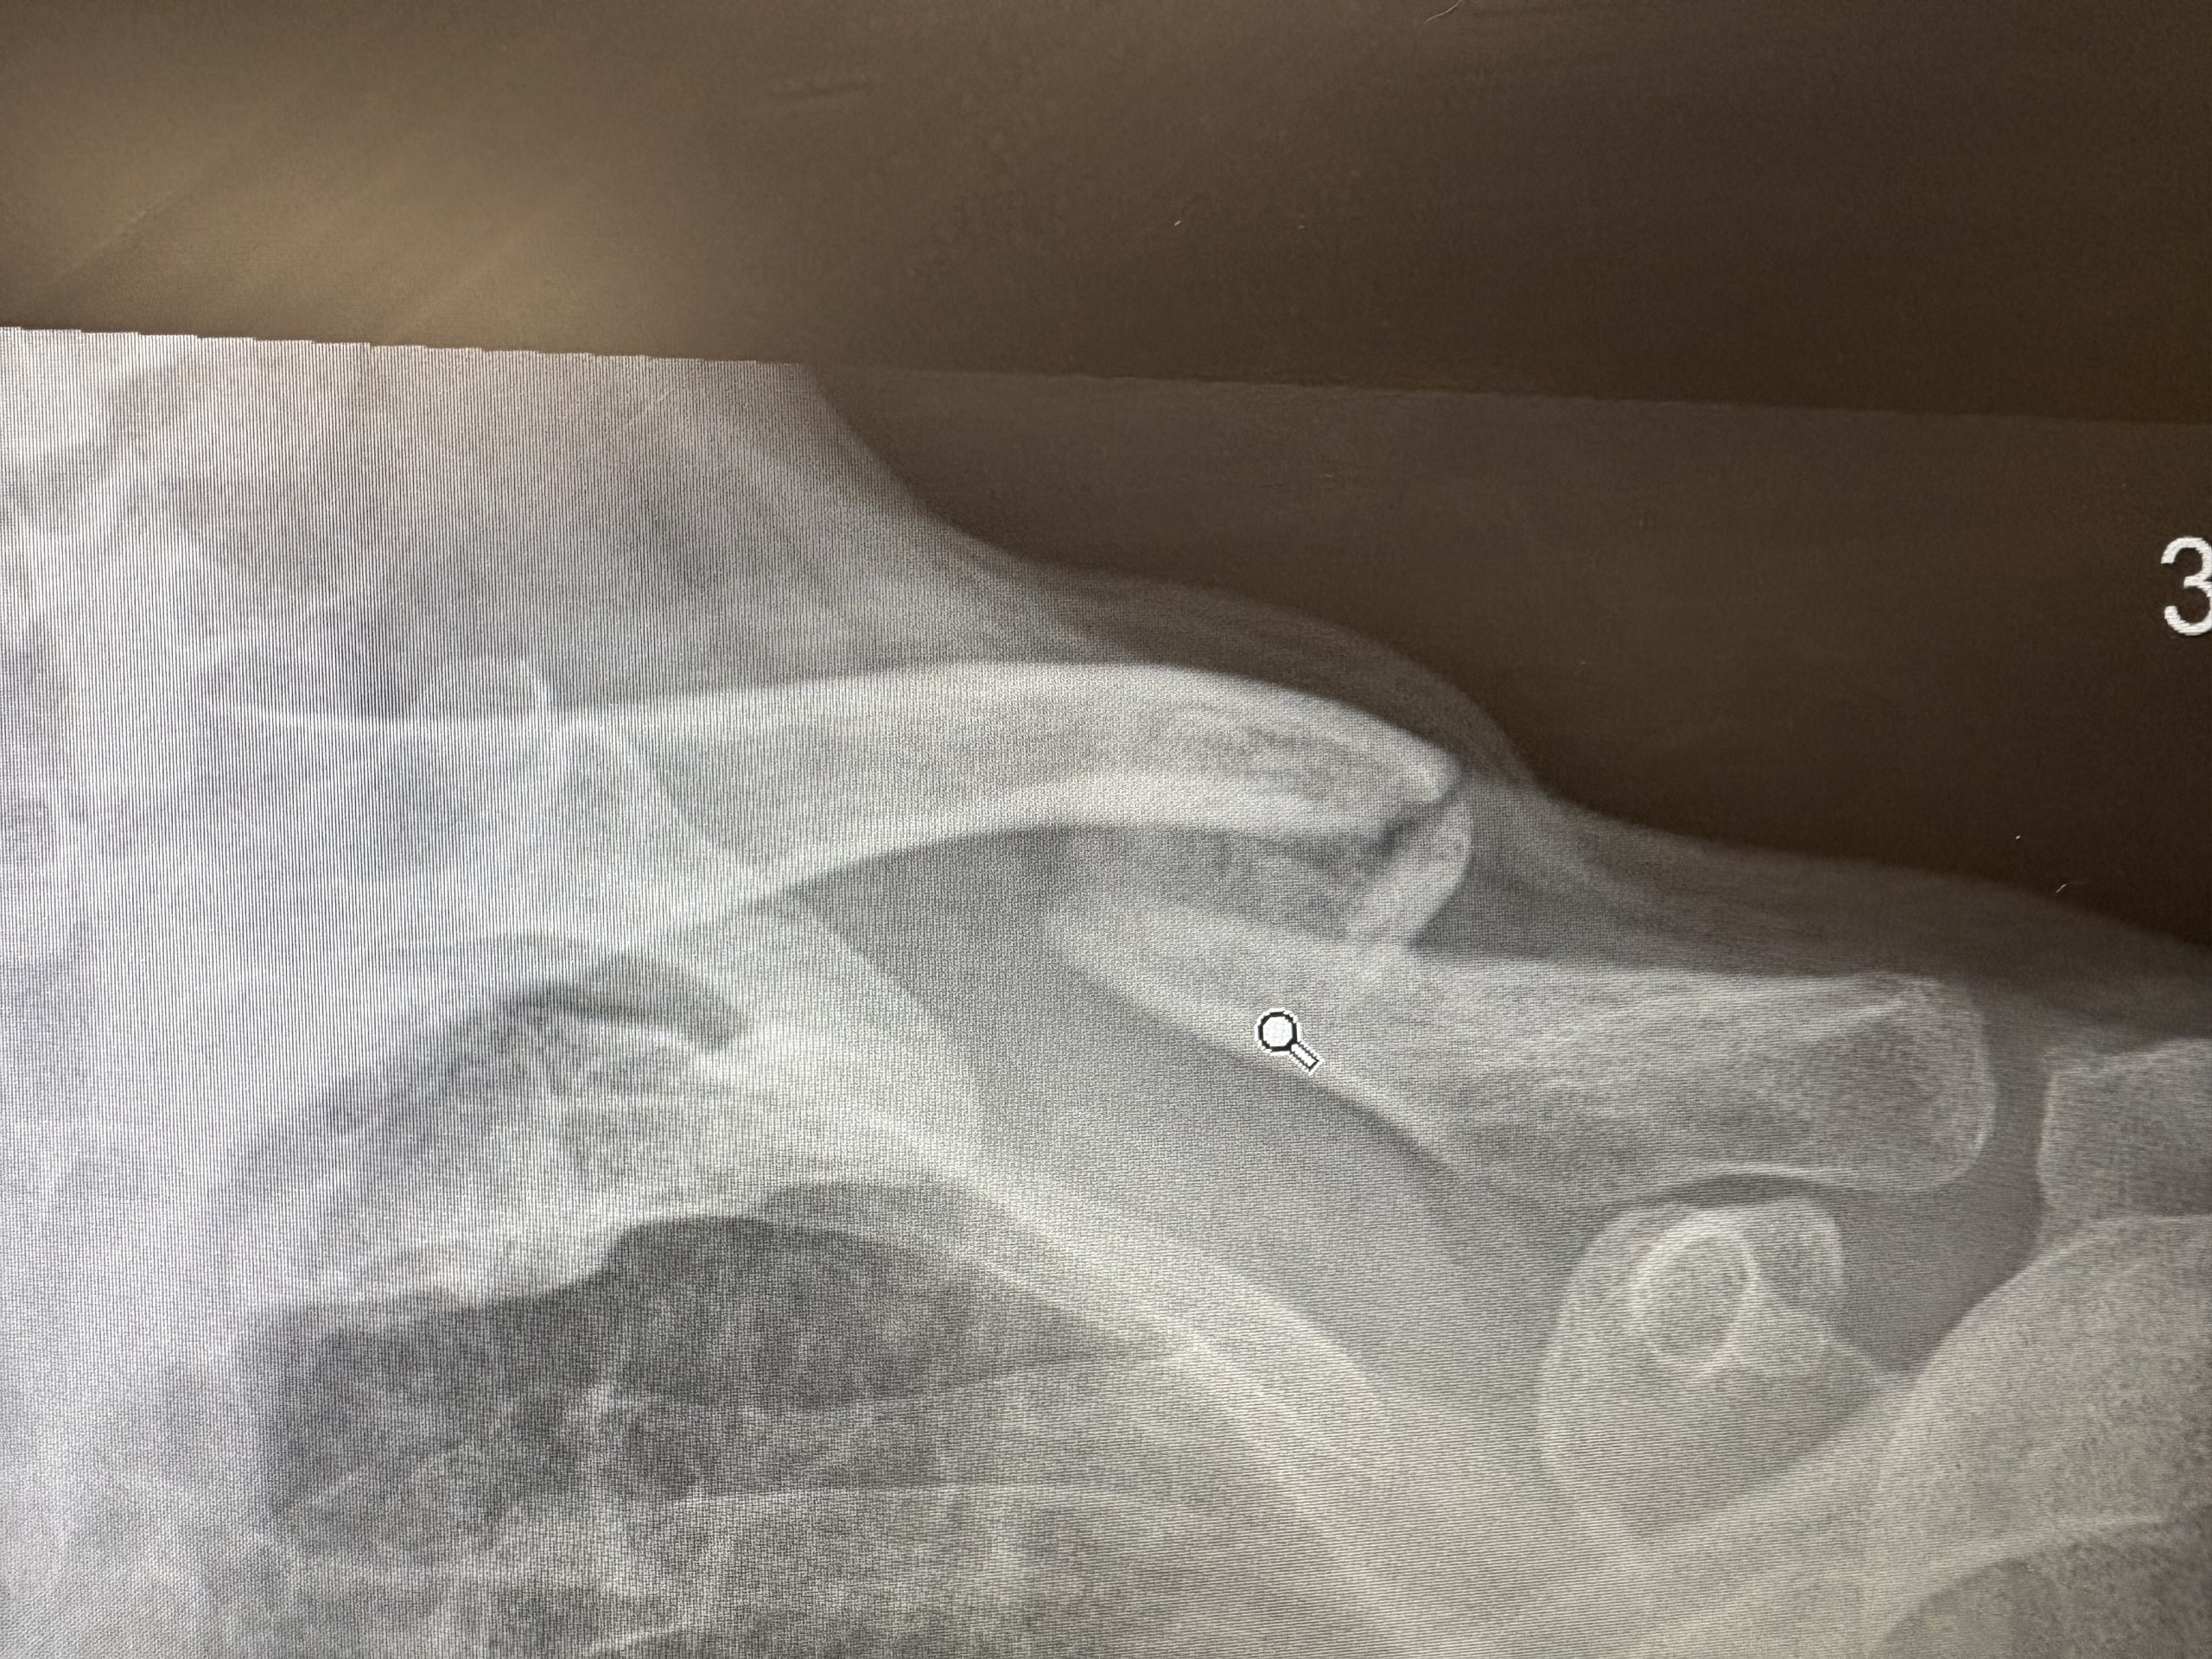

Two years ago I wrote this. It concluded ” And after today nothing else could go wrong surely?”. Consider this image as the first challenge to that assertion. It won’t be the last.